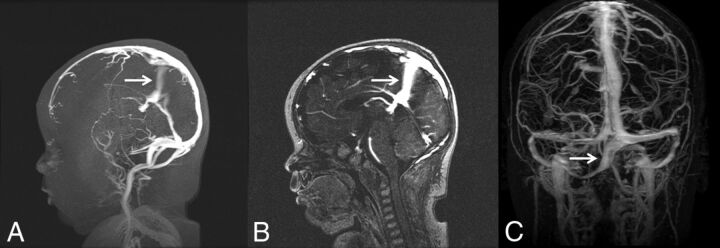

FIG 5.

Examples of embryonic sinuses. Persistent falcine sinus in a 2-month-old infant seen on 3D-MRV (A) and a sagittal section of 2D-MRV (B, arrows). C, Occipital sinus (arrow).

The following data are summarized in Table 3. A persistent falcine sinus was observed in 8.0% of the younger than 1-year age category. This percentage trended downward to 1.4% of the 16- to 20-year age category, yet the difference between groups did not reach statistical significance (P = .09). A similar downward trend was noted with the occipital sinus, which was present in 24.0% of the younger than 1-year population and trended downward to 2.8% of the 16- to 20-years of age category (P < .0001). A sample MRV of a persistent falcine sinus and occipital sinus is demonstrated in Fig 5.